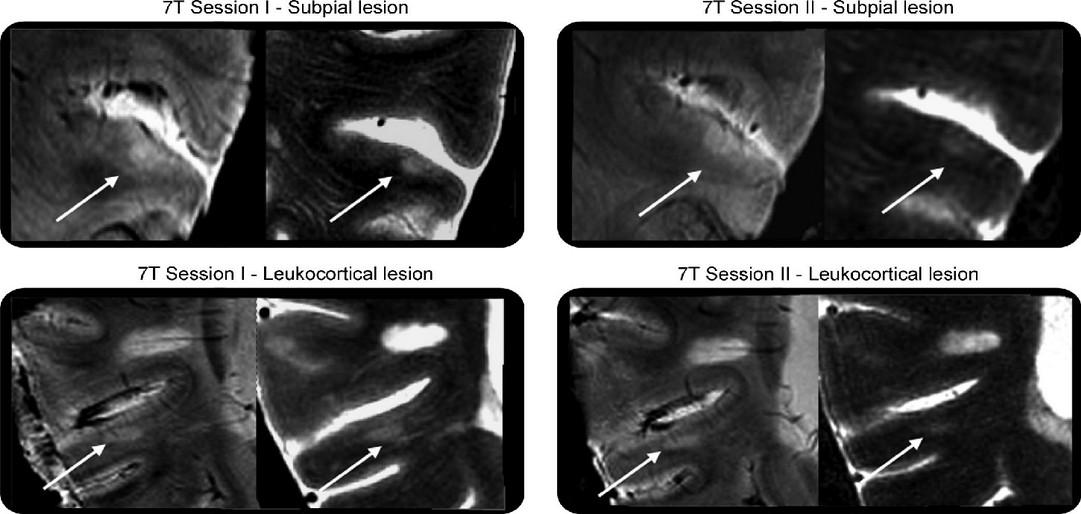

Advanced Imaging biomarkers for MS progression

Chronic pathology within existing lesions slowly expanding/evolving lesions

Microglial activation

transfer ratio1, 7 Tesla MRI2 , Deformation-based (Jacobian) analysis using conventional T2- and T1- weighted images3 , susceptibility-weighted imaging (SWI)4 and quantitative susceptibility mapping (QSM)4